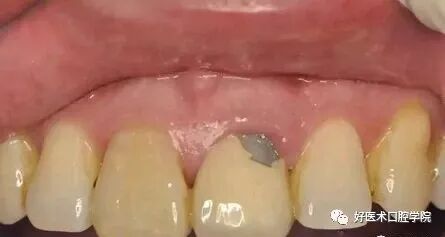

前牙修复美学问题:

对于前牙美观要求程度高而患者局部牙槽骨缺损的患者(多是因为缺牙时间长或者拔牙抠根时候破坏了牙槽骨),镶烤瓷牙不能加牙龈瓷了事。牙龈瓷和正常牙龈有一定色差,看起来非常不自然,且因为牙龈瓷悬空容易折断,折断后无法修理。对于有经济实力的患者可先植骨,3个月后牙槽骨稳定后再镶牙;经济实力差些的可以植入粘膜恢复缺损后即可镶牙,粘膜取患者自体上腭粘膜。